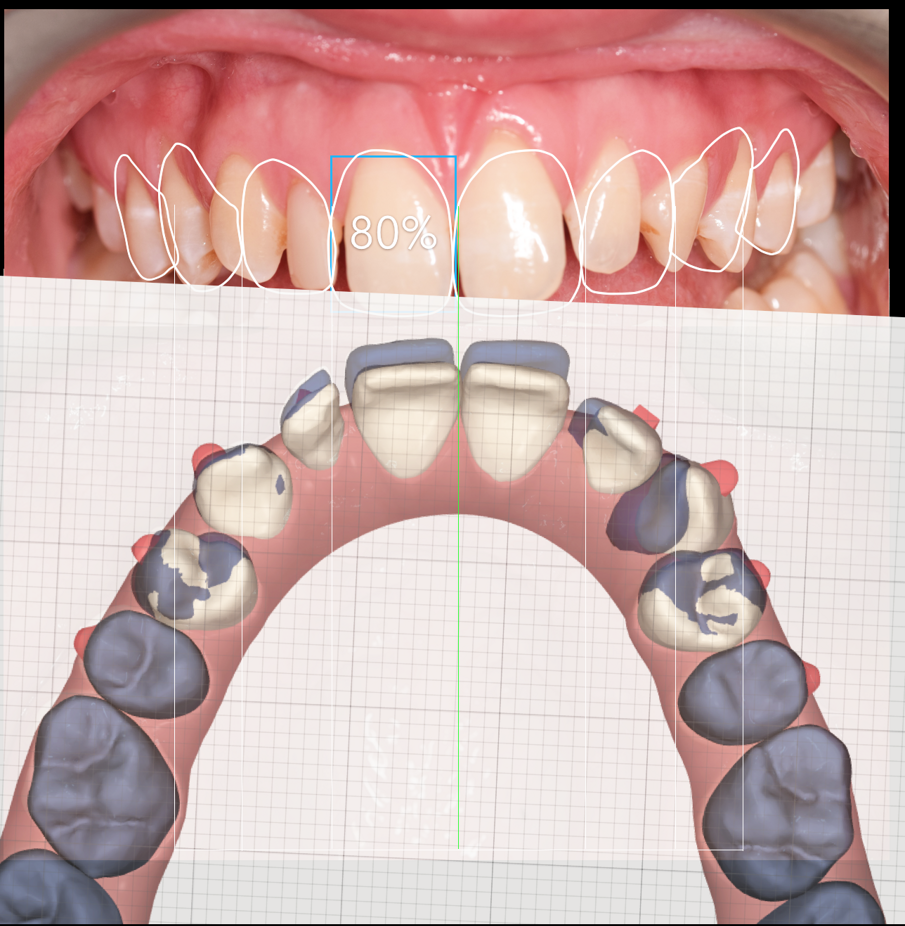

A treatment plan was constructed based on a facially driven smile design, with calibrated images measured against the invisalign clincheck software. The benefit to using a digital system here was to allow for accurate positioning of the anterior teeth for minimal preparation and the ideal restorative outcome. (Figs. 1a-f)

A 7 week invisalign programme allowed for enough movement in the upper arch, while resolving the mild crowing in the lower arch. The final tooth position can be seen in figure 1f.